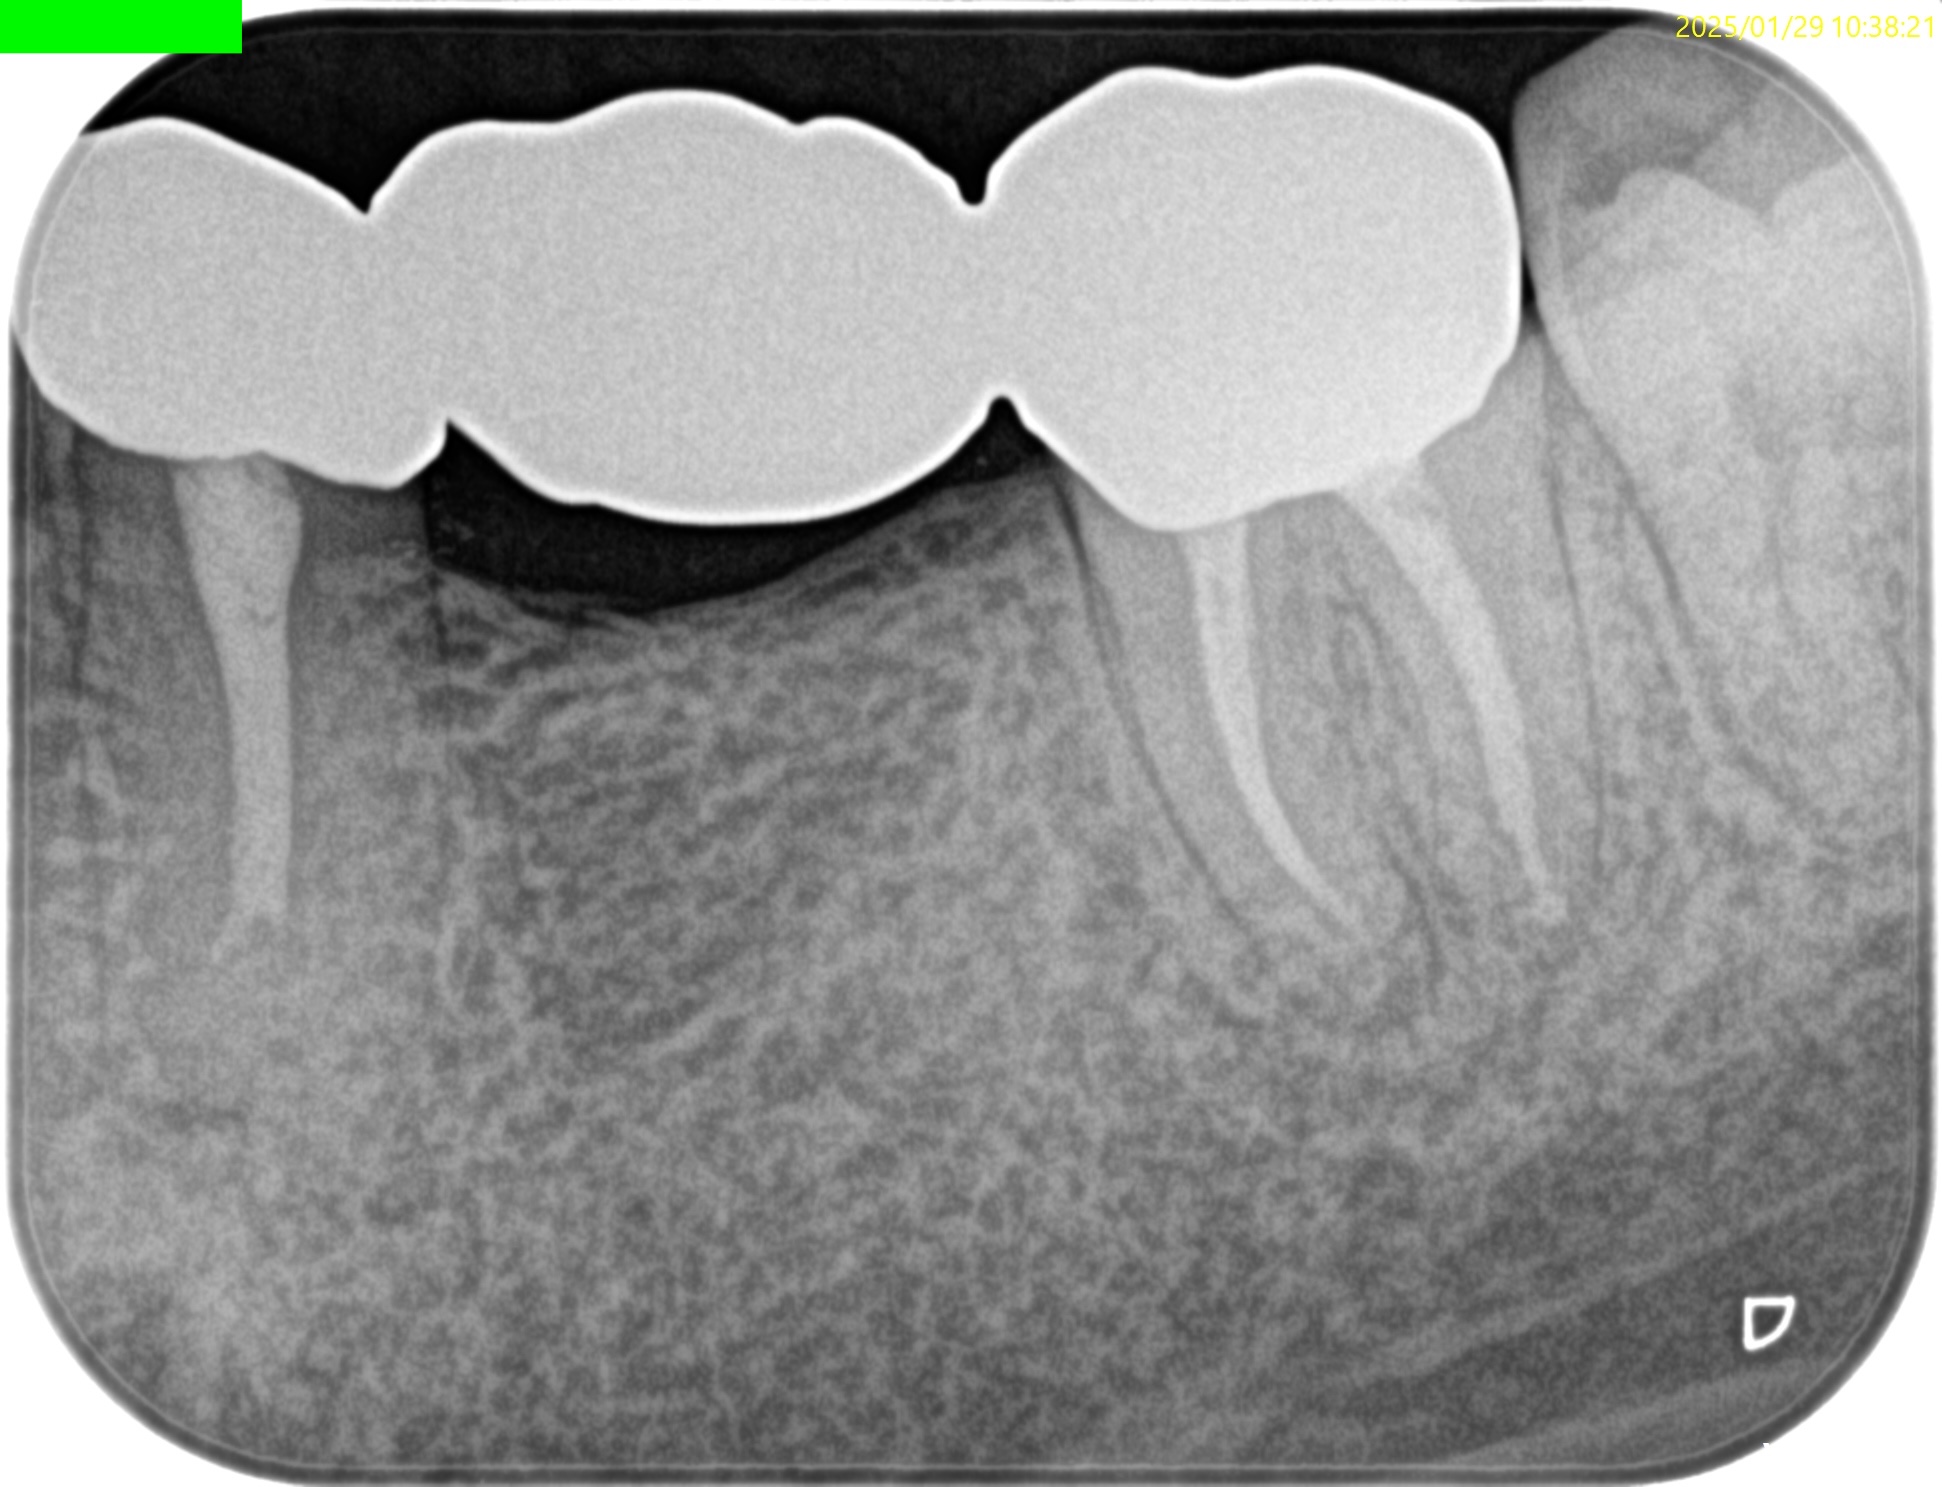

Post-op 1yr recall(2025.1.29)

術前のSinus tract, 打診痛は消失した。

初診時と比較した。

大きく状況は改善された。

ということで経過観察も終了でいいだろう。